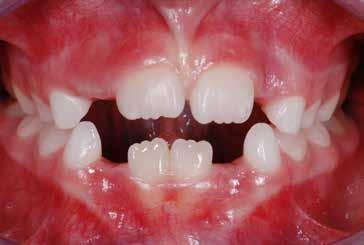

Presentazione del caso > F.V, bambino di cinque anni, presenta una malocclusione di II Classe scheletrica, III Classe dentale molare e canina destra e sinistra, morso inverso anteriore. Le arcate dentali mostrano usura degli elementi dentari anteriori a causa dell’occlusione patologica. Le linee mediane, superiore ed inferiore, sono centrate; il frenulo labiale superiore patologico per un’eccessiva estensione inter-incisale.

Il piano di trattamento prevede l’utilizzo di un dispositivo elastodontico di III Classe, da portare per due ore diurne e tutte le notti in modo passivo, senza effettuare alcun esercizio, al fine di ripristinare una relazione molare e canina bilaterale di I Classe ed il corretto avanzamento maxillare e inibire l’eccessiva crescita mandibolare. È possibile ottenere il risultato in pochissimi mesi di terapia, essendo la crescita del paziente molto attiva.

In un secondo momento, alla risoluzione della problematica scheletrica, si monitorizzerà il caso con visite semestrali in modo da reintervenire qualora si dovesse ripresentare la problematica.

Dall’esame clinico si evince la III Classe dentale, l’inversione anteriore e l’over-jet negativo.

Una volta ottenuta la correzione del rapporto molare ed incisale, l’apparecchio elastodontico verrà portato dal paziente solo durante la notte per stabilizzare il risultato ottenuto e guidare l’eruzione degli elementi dentari per un totale di quattordici mesi di terapia. ad inizio trattamento :

Considerazioni > L’analisi cefalometrica ad inizio trattamento dimostra la II Classe scheletrica con protrusione del mascellare superiore e prognazia mandibolare; tendenza alla crescita verticale. L’esame clinico evidenzia una protrusione mandibolare funzionale.